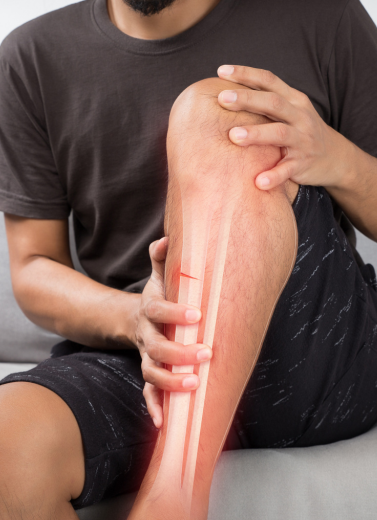

Accidents Happen. We’re Here to Fix Them — Expert Fracture & Trauma Care in Patna

Bone fractures and trauma injuries need quick, accurate, and expert treatment to avoid long-term disability or improper healing. At our Fracture & Trauma Department, Dr. Anand Bhushan provides specialized care for all types of fractures — from simple to highly complex — using advanced surgical and minimally invasive techniques.

We Treat All Types of Bone Injuries and Trauma Cases

Simple / Compound Fractures

Complex & Comminuted Fractures